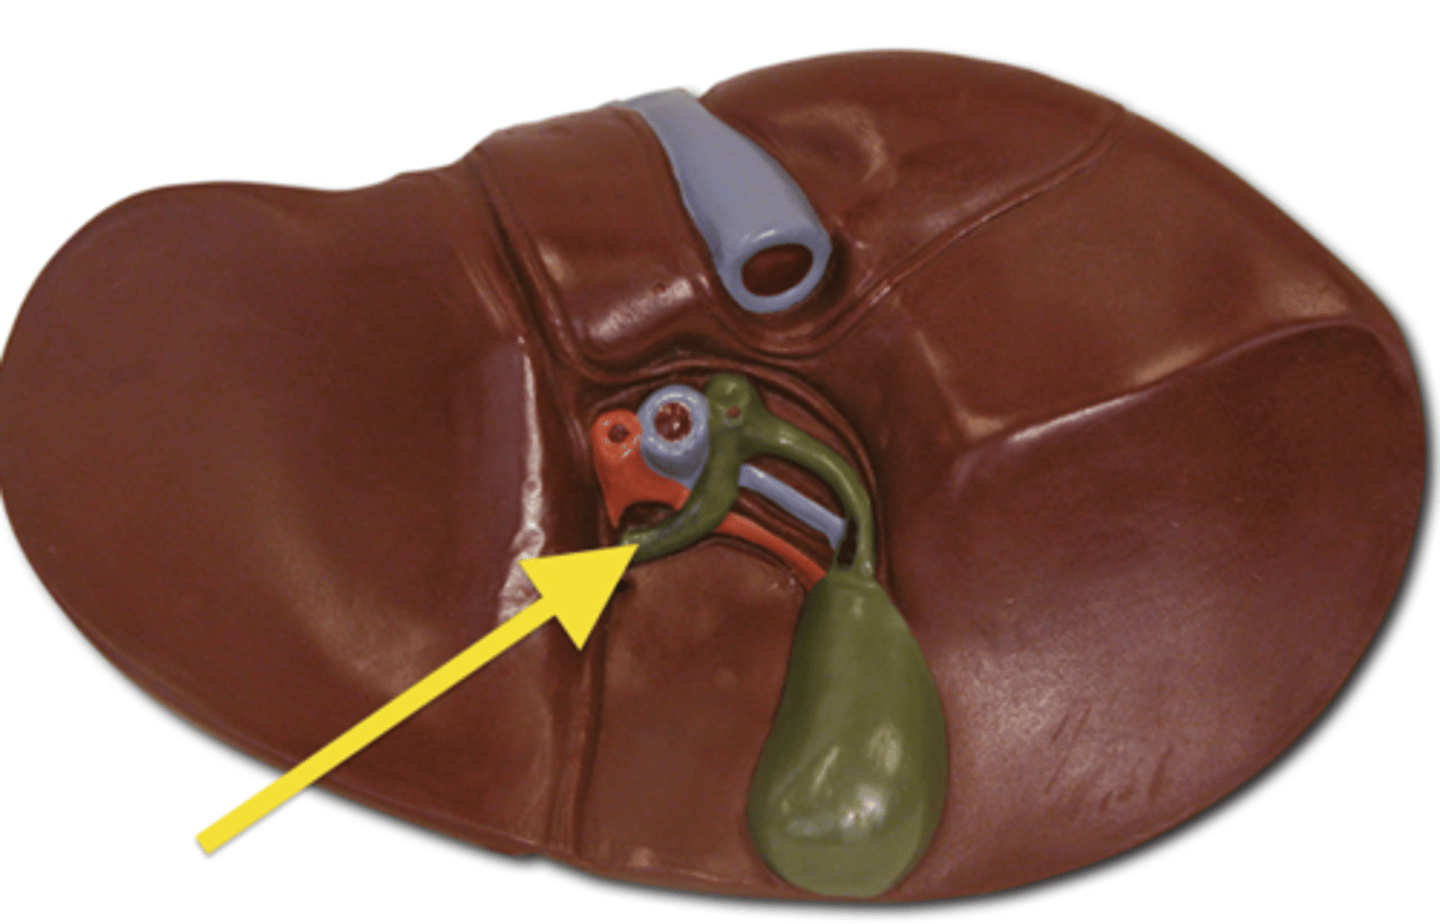

liver

pin

cystic duct

common hepatic duct

Gallbladder

portal vein

pancreatic duct

common bile duct

hepatopancreatic sphicter / duodenal papilla